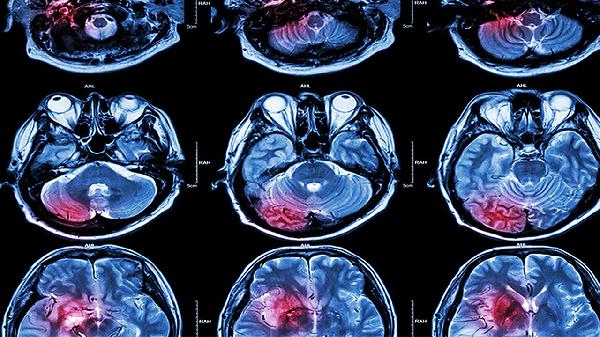

脑血栓片的作用机理主要有抗血小板聚集、改善脑微循环、保护脑神经细胞、溶解血栓、调节血脂等。该药为复方制剂,需严格遵医嘱使用。

尿激酶样物质能激活纤溶酶原转化为纤溶酶,降解纤维蛋白网状结构,促进已形成血栓的溶解。该作用针对急性期血栓效果显著,但需在发病6小时黄金时间窗内使用,并配合影像学评估。